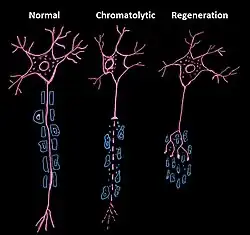

In cellular neuroscience, chromatolysis is the dissolution of the Nissl bodies in the cell body of a neuron. It is an induced response of the cell usually triggered by axotomy, ischemia, toxicity to the cell, cell exhaustion, virus infections, and hibernation in lower vertebrates. Neuronal recovery through regeneration can occur after chromatolysis, but most often it is a precursor of apoptosis. The event of chromatolysis is also characterized by a prominent migration of the nucleus towards the periphery of the cell and an increase in the size of the nucleolus, nucleus, and cell body.[1] The term "chromatolysis" was initially used in the 1940s to describe the observed form of cell death characterized by the gradual disintegration of nuclear components, a process which is now called apoptosis.[2] Chromatolysis is still used as a term to distinguish the particular apoptotic process in the neuronal cells, where Nissl substance disintegrates.

Central chromatolysis is the most common form of chromatolysis and is characterized by the loss or dispersion of the Nissl bodies starting near the nucleus at the center of the neuron, and then extending peripherally towards the plasma membrane. Also characteristic of central chromatolysis is the displacement of the nucleus towards the periphery of the perikaryon.[3][4][5] Other cellular changes are observed during the process of the central chromatolysis. The process of Nissl dissolution is less apparent toward periphery of the cell body of the neuron, where normal-looking Nissl bodies may be present.[1] Hyperplasia of neurofilaments is frequently observed, however the extent varies. The number of autophagic vacuoles and lysosomal structures often increase during central chromatolysis. Changes can also occur in other organelles such as the Golgi apparatus and neurotubules. However, the exact significance of these changes is currently unknown. In neurons receiving axonal transection, central chromatolysis is observed in the area between the nucleus and the axon hillock following.[6]

Peripheral chromatolysis is much less common, but has been reported to occur after axotomy and ischemia in certain species. Peripheral chromatolysis is essentially the reverse of central chromatolysis, in which the disintegration of Nissl bodies is initiated at the periphery of the neuron and extends inwards towards the nucleus of the cell. Peripheral chromatolysis has been observed to occur in lithium-induced chromatolysis and it could be useful in investigating and countering the hypothesis that waves of enzymatic activity always progress from the perinuclear area, or the area situated around the nucleus, to the peripheral of the cell.[7]